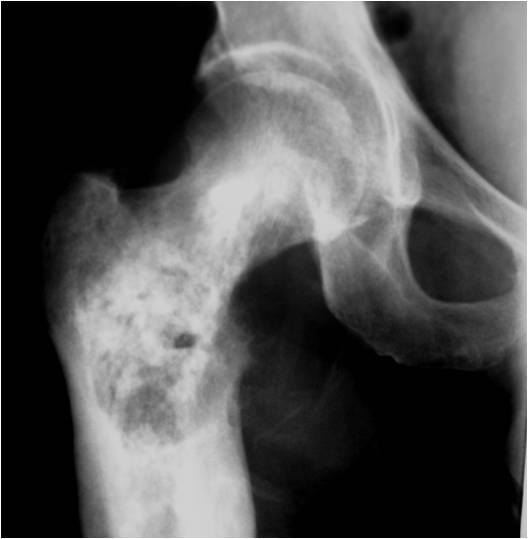

Radiology emulates pathology: Biphasic Tumor

- One region low grade chondrosarcoma

- Second more aggressive area with bone destruction, lysis of calcification, soft tissue mass

- Cortical permeation and a soft tissue mass in 70% of cases

Ill-defined, lytic intraosseous lesion

- Or extraosseous soft tissue mass

- Devoid of calcifications in continuity with lesions having the features of a cartilaginous tumor

Characteristically abrupt transition between chondroid tumor and dedifferentiated, lytic component

Bone may be expanded and adjacent cortex thickened

(Right Arrow)Aggressive Lytic Area (Dedifferentiated Sarcomatous Component) Cortical Destruction Soft Tissue Mass without Calcification